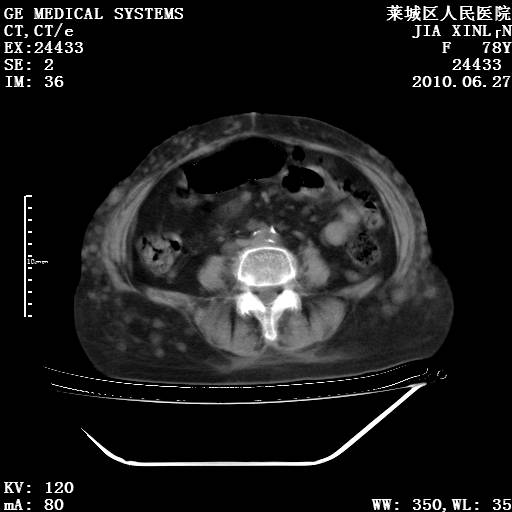

以下是引用胡宇在2010-7-2 19:11:00的发言:[br]神经纤维瘤的特点为:肿块呈多发性、数目不定,少的几个,多的可成百上千难以计数。小的如米粒,大的似拳头,甚至可达十数公斤以上。可松弛地悬挂于皮表,皱褶及松弛可致畸形明显。神经纤维瘤沿神经干的走向生长时呈念珠状,或蚯蚓块状形结节。此外神经纤维瘤皮肤可出现咖啡斑,大小不一,形如雀斑小点状,或大片状,分布与神经纤维瘤肿块的分布无关。肿瘤数目不多的患者,皮肤色素咖啡斑状沉着是纤维神经瘤的重要诊断之一。 本病多发于躯干,有时出现于四肢及面部,患者常合并许多疾病应予重视加以区别。 [br] [br] [br] [br]lyb999说 [br]